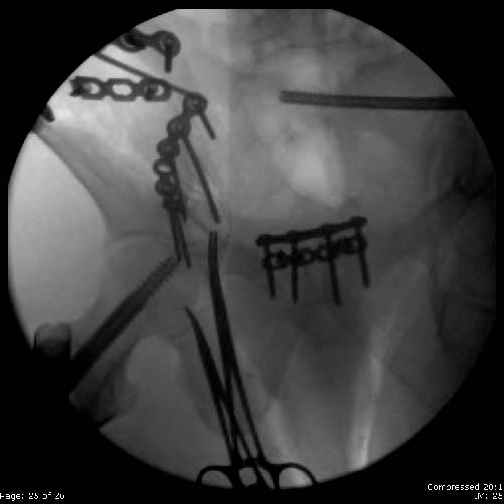

Here are the postop fluoros.

Reduced the triangular wedge piece of iliac wing to posterior intact ilium (crescent), held w/k-wire, then used 3-hole push plate to keep from moving, lagged from lat-med w 3.5 screw.

Then 6-hole plate along brim with 1 screw in R sacral ala. Then lagged 2 screws along crest A --> P. finally 10-hole plate along inner aspect of crest. R posterior ilium still a bit stepped off.

Fluoroed L SI joint and it seemed stable, but wide. So, applied c-clamp to try to squeeze down L SI joint (and note, on the last slide attached, that it's still wide), and got it closer. Single perc Iliosacral screw 40mm thread.

Applied second plate anteriorly on symphysis as I wasn't confident L SI was as stable as it could be and wanted to protect it better.